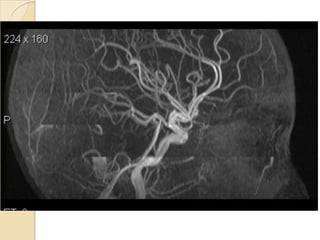

Arteries of the brain (lateral view) - MRA

1. Anterior cerebral artery

2. Anterior communicating artery

3. Basilar artery

4. branches (in insula) of middle cerebral artery

5. Cavernous portion of internal carotid artery

6. Cervical portion of internal carotid artery

7. Genu of middle cerebral artery

8. Intracranial (supraclinoid) internal carotid artery

9. Middle cerebral artery

10. Ophthalmic artery

11. Petrous portion of internal carotid artery

12. Posterior cerebral artery

13. Posterior cerebral artery in ambient cistern

14. posterior cerebral artery in interpeduncular

cistern

15. Posterior communicating artery

16. Posterior inf cerebellar artery.

17. Quadrigeminal portion of posterior cerebral

artery

18. Superior cerebellar artery

19. Vertebral artery